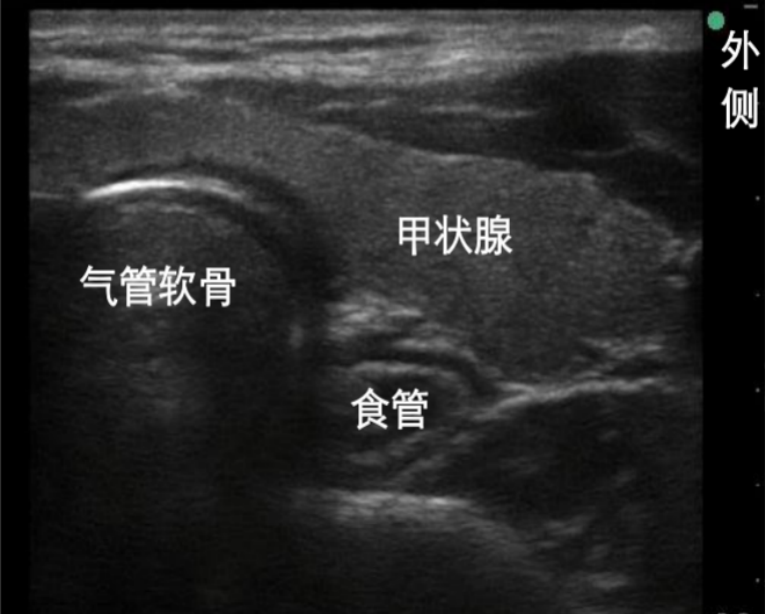

6. 气管软骨平面的扫查

在环状软骨下方即为气管软骨。如果选择高频线阵探头做矢状面扫查,气管软骨为低回声的圆形结构。通常在颈部可以看见6个气管软骨环。气管上组织为皮肤、皮下脂肪、骨骼肌。在2~3软骨环还可以发现甲状腺峡部的存在。此时打开多普勒,可以发现高速颈内动脉的血流。气管软骨环为低回声,矢状面为串珠样存在,横切面为马蹄形(倒U型),由于空气黏膜的存在,会有显著的高回声和后方的伪影。图10右上为气管软骨层面扫查横向切面,图10下为气管软骨平面扫查的矢状面,深蓝色为甲状软骨,绿色为环甲膜,红色为环状软骨,淡蓝色为气管软骨。

图片

图10  气管软骨平面的扫查和切面